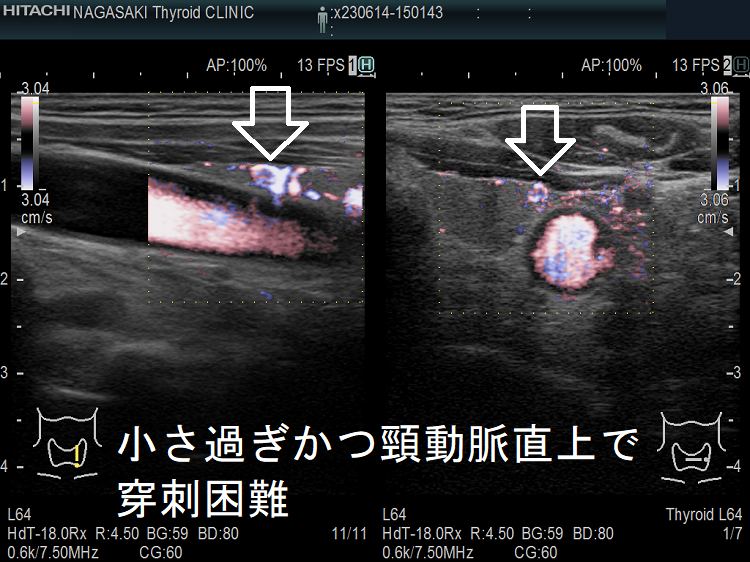

- 頚動脈に接する小さな甲状腺腫瘍

- 頚動脈近傍で、頸動脈に連鎖して拍動する小さな甲状腺腫瘍

甲状腺乳頭癌の可能性があるため、穿刺細胞診したくても、頚動脈や気管を刺してしまう危険を考えれば断念するのが正しいと思います。「退く勇気」も大切なのです。その代わり、甲状腺腫瘍が大きくならないか、腫瘍マーカーは上昇しないか、定期的に経過を見る必要があります。